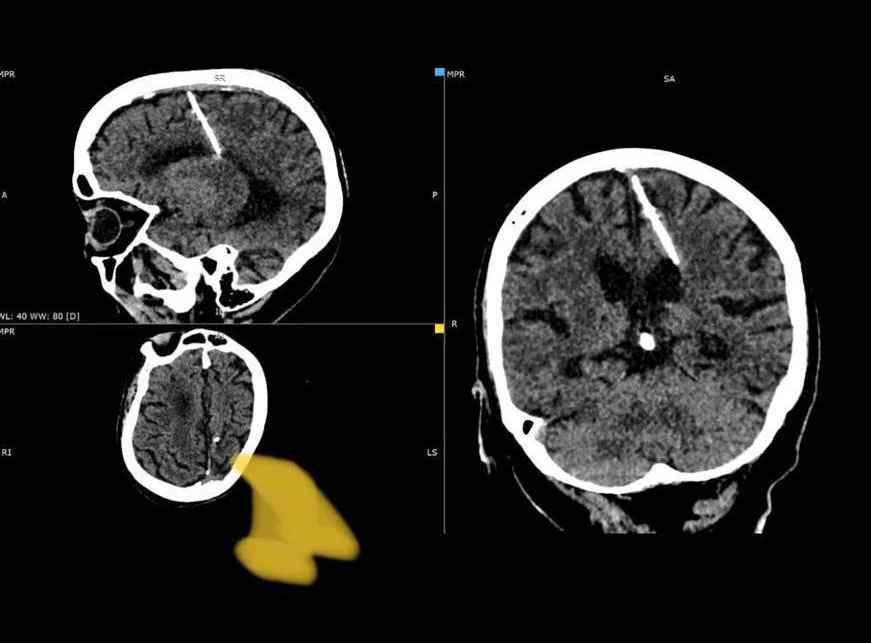

Трехсантиметровую иглу обнаружили сахалинские врачи в мозгу у 80-летней женщины.

Как сообщает пресс-служба областного минздрава, инородное тело в голове у пациентки нашли во время проведения компьютерной томографии.

«Женщина живет с инородным телом с рождения, таким образом родители решили умертвить ребенка в сложное военное время. Такие случаи в голодные годы были не редкостью: младенцу в родничок вставлялась тонкая игла, которая повреждала мозг. Родничок быстро затягивался, скрывая следы преступления, а малыш погибал», – отметили в минздраве.

Как уточнили специалисты, игла проникла в левую теменную долю, однако, несмотря на это, девочка выжила. Более того, на протяжении жизни сахалинку даже не беспокоили головные боли, и врачи обнаружили иглу случайно. Сейчас женщина чувствует себя хорошо, угрозы ее здоровью нет. Медики решили не удалять инородное тело, так как, по их мнению, операция может ухудшить состояние пациентки.